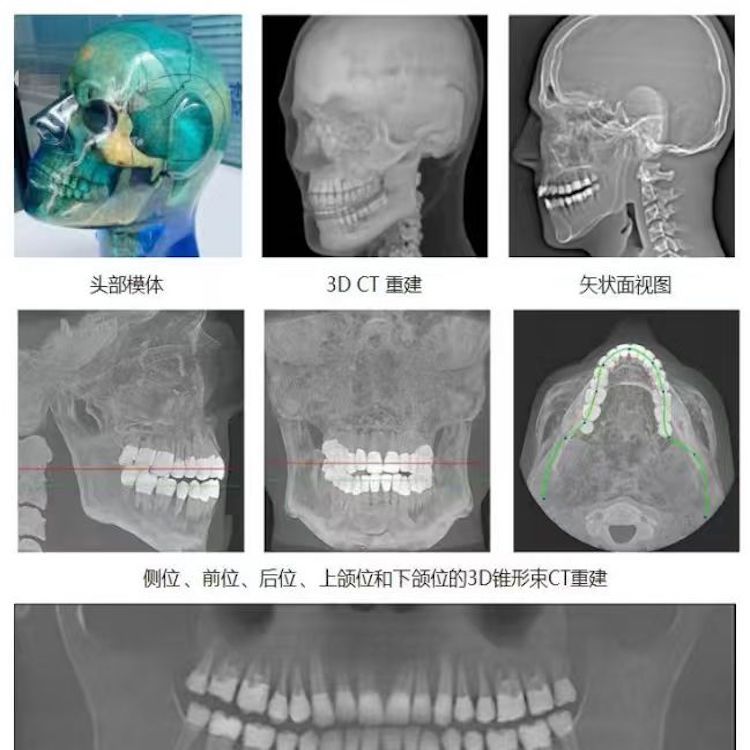

頭部模體是頭部診斷放射學(xué)的參考標(biāo)準(zhǔn),該模體旨在協(xié)助技術(shù)和臨床人員,在大多數(shù)需要精細(xì)解剖細(xì)節(jié)的放射學(xué)程序中選擇、監(jiān)測(cè)、培訓(xùn)和驗(yàn)證掃描參數(shù)。 模體為研究人員、臨床醫(yī)生和技術(shù)人員提供了一致性的工具。它非常適合確定最佳系統(tǒng)設(shè)置、調(diào)試新設(shè)備、監(jiān)測(cè)系統(tǒng)性能和培訓(xùn)牙科X射線、全景X射線、CT和錐束CT程序。 這個(gè)模體包括一個(gè)可調(diào)節(jié)的支架,用于在錐束 CT 或全景X射線系統(tǒng)中定位。模體的下頜略微張開(kāi),前牙垂直排列,以復(fù)制正確的咬合引導(dǎo)定位 。 請(qǐng)注意,實(shí)際咬合引導(dǎo)無(wú)法在這個(gè)產(chǎn)品中定位。 頭部模體是由專有組織等效材料制成的。由組織模擬樹脂制成,這些樹脂模擬X射線對(duì)人體的衰減特性,適用于CT和治療能量范圍(50keV-25MeV)。 模體在大小和結(jié)構(gòu)上都近似于平均男性頭部 。該模體包括詳細(xì)的3D擬人化解剖結(jié)構(gòu), 包括大腦、骨骼、喉、氣管、鼻竇、鼻腔和牙齒。骨骼包括皮質(zhì)和骨小梁的分離。牙齒包括明顯的牙本質(zhì)、牙釉質(zhì)和包括神經(jīng)的牙根結(jié)構(gòu)。鼻竇完全張開(kāi)。

頭部模體特點(diǎn) 1. 詳細(xì)的解剖特征; 2. 確定法蘭克福平面以確保正確對(duì)齊; 3. 50 keV 至 25 Mev 的組織等效值; 4. 具有六個(gè)自由度的定位支架; 5. 包括泡沫內(nèi)襯手提箱; 6. 12個(gè)月保修。

功能和應(yīng)用 1. X射線 ,全景X射線 ,CT和錐束CT系統(tǒng); 2. 學(xué)習(xí)如何正確定位頭部以獲得最佳圖像; 3. 測(cè)試重建技術(shù)和算法 ,用于植入物規(guī)劃和頜面部重建; 4. 在實(shí)施新設(shè)備和新技術(shù)期間培訓(xùn)并評(píng)估人員; 5. 驗(yàn)證圖像質(zhì)量的一致性。